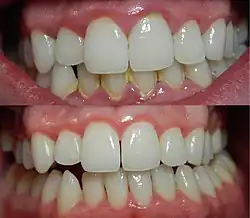

Gingivitis before (top) and after (bottom) a thorough mechanical debridement of the teeth

The focus of treatment is to remove plaque. Therapy is aimed at the reduction of oral bacteria and may take the form of regular periodic visits to a dental professional, together with adequate oral hygiene home care. Thus, several of the methods used in the prevention of gingivitis can also be used for the treatment of manifest gingivitis, such as scaling, root planing, curettage, mouth washes containing chlorhexidine or hydrogen peroxide, and flossing. Interdental brushes also help remove any causative agents.[25]